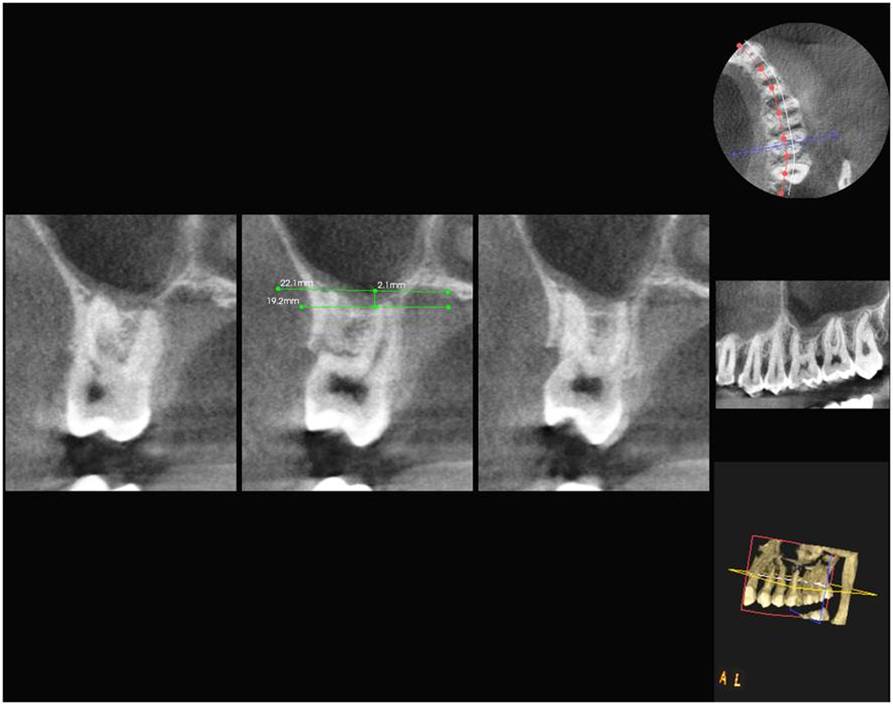

Results: In cases of classification 0, 85% and in classification 1 , 55.3% cases shows similar classification in both OPG and DVT. 28.5% of cases in both imaging modalities show classification 2. Only 15.9% of teeth roots exhibits classification 3. 11.1% of cases showed classification 4.The panoramic radiograph showed a statistically significant 2.24 times longer root projection on the sinus cavity in OPG comparison to DVT images.

Conclusion: Teeth roots projecting in to the sinus in OPG, shows no vertical protrusion in to the sinus in DVT images. Hence DVT was better than OPG with measurements that were more exact and closer to anatomical reality.